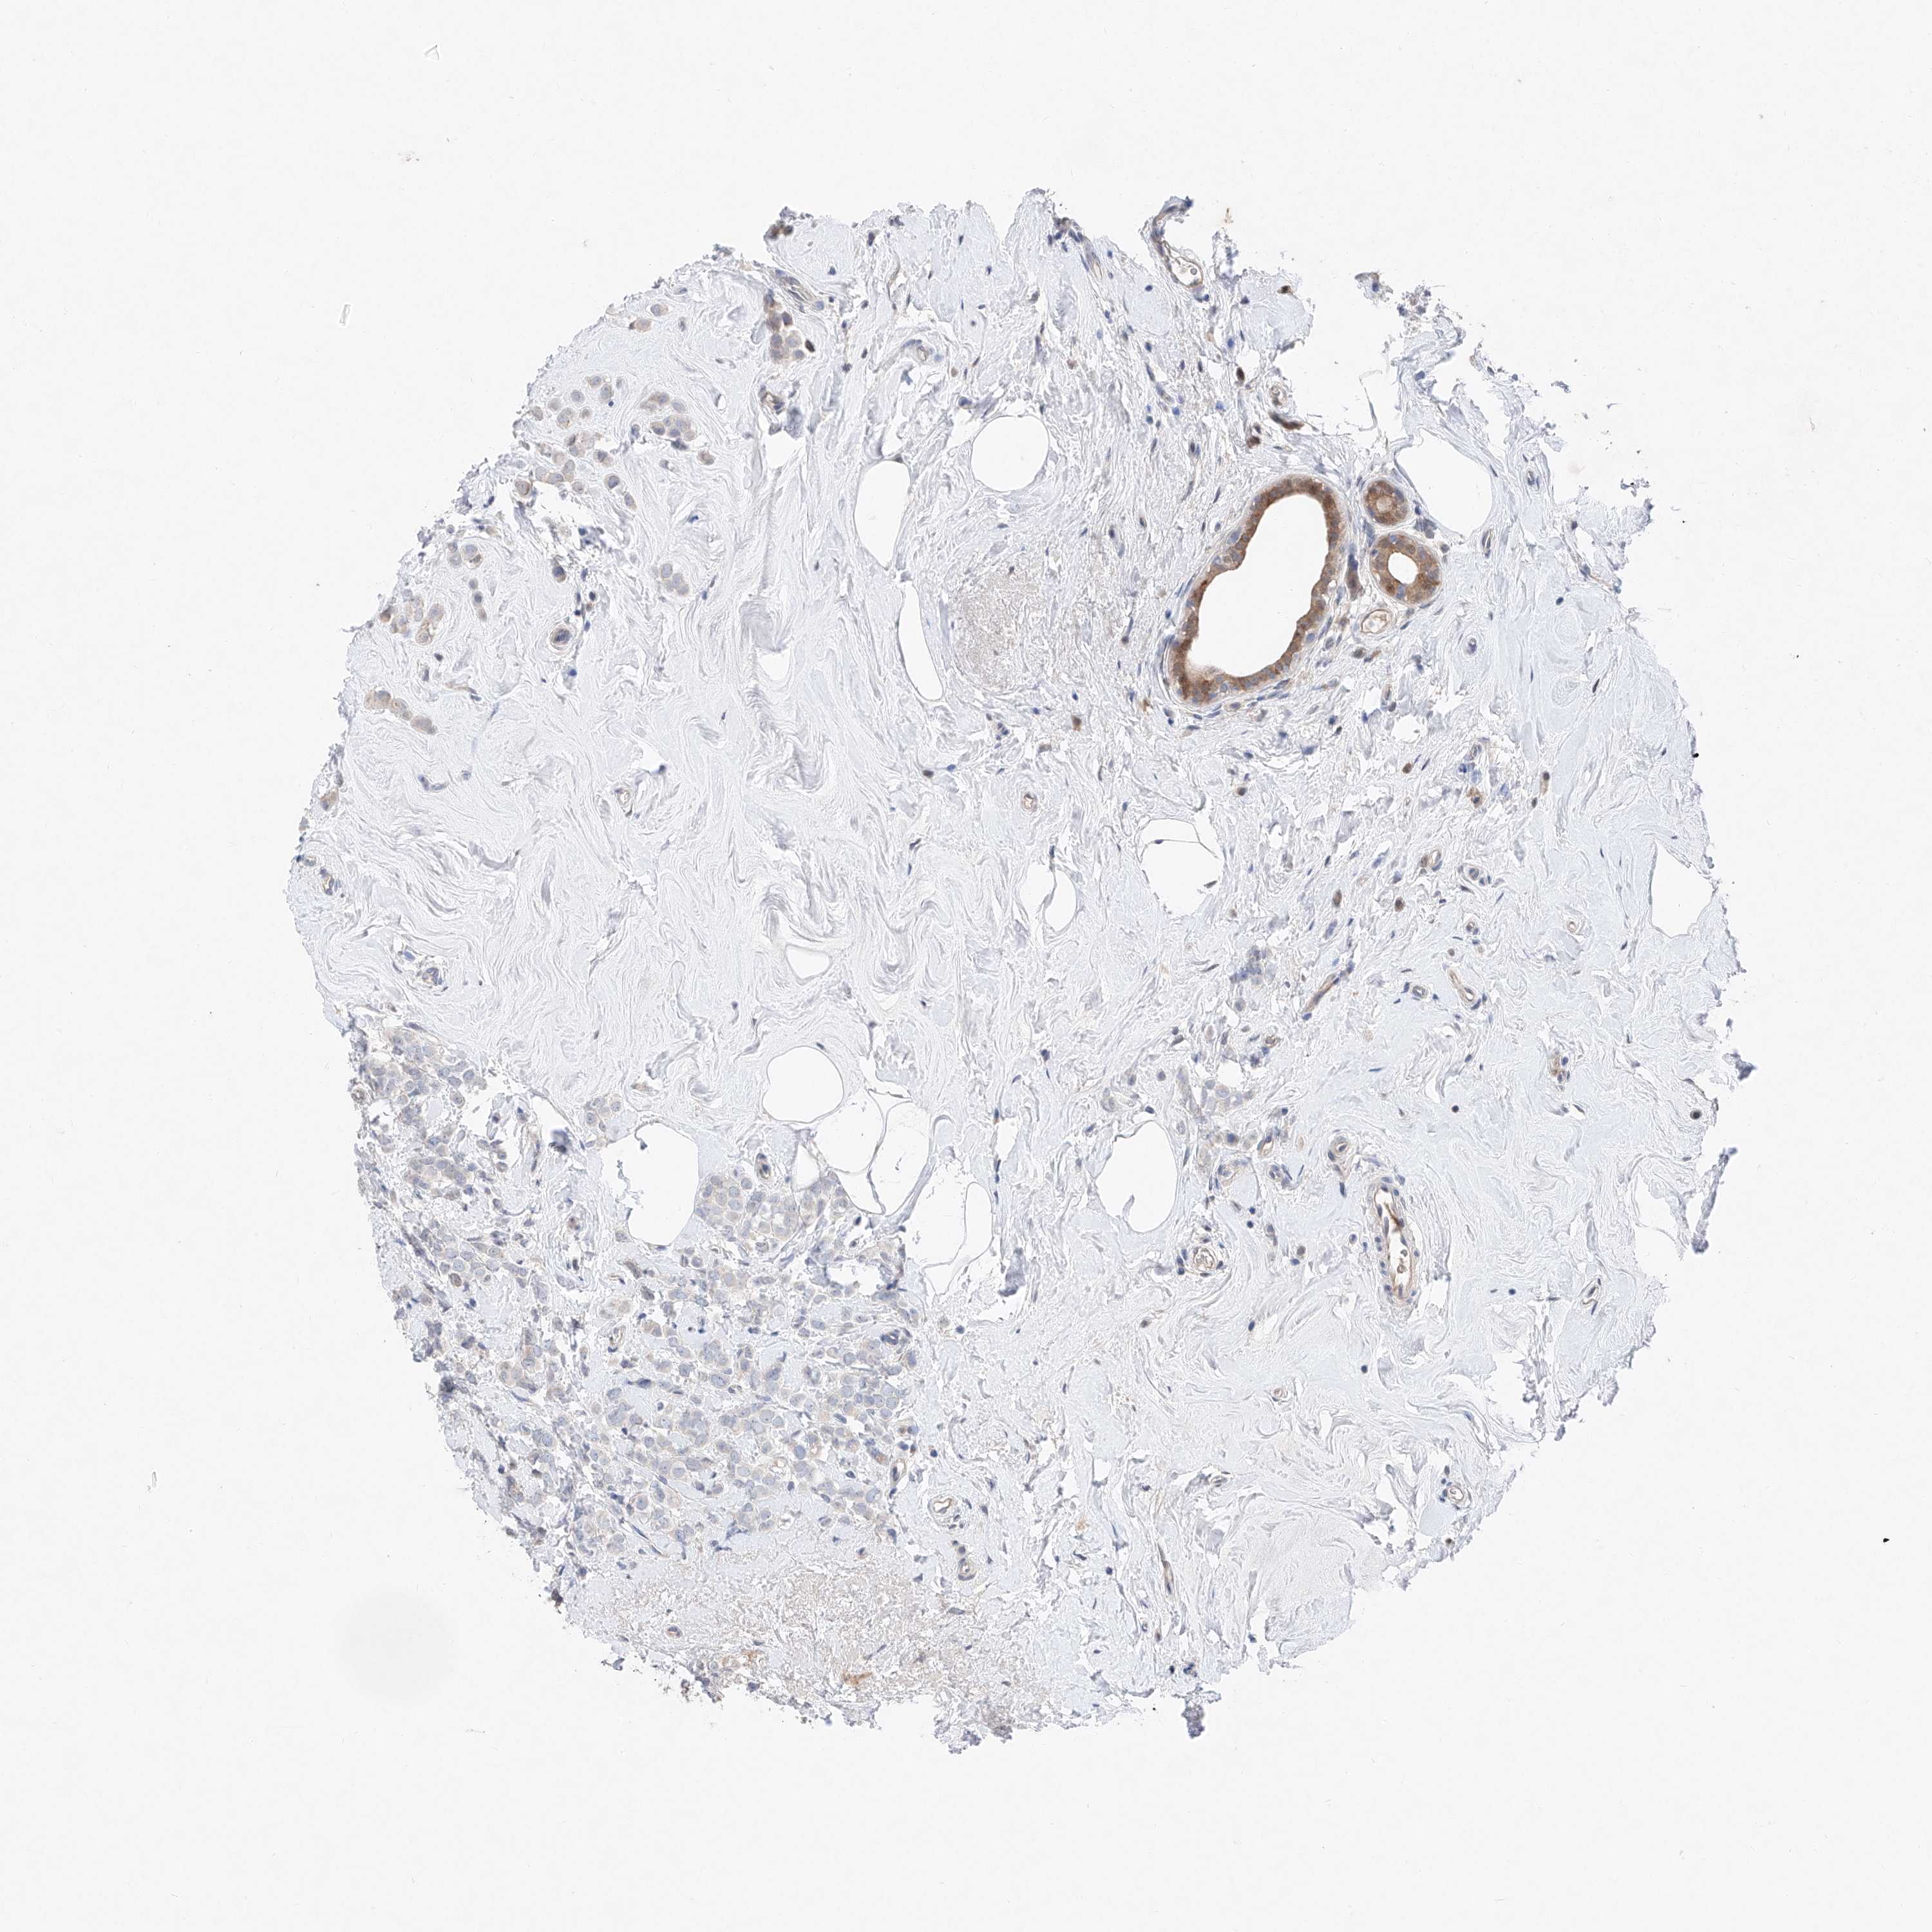

BRCA TCGA BRCA VALIDATION PROTEIN EXPRESSION

ANTIBODIES

AND

VALIDATION